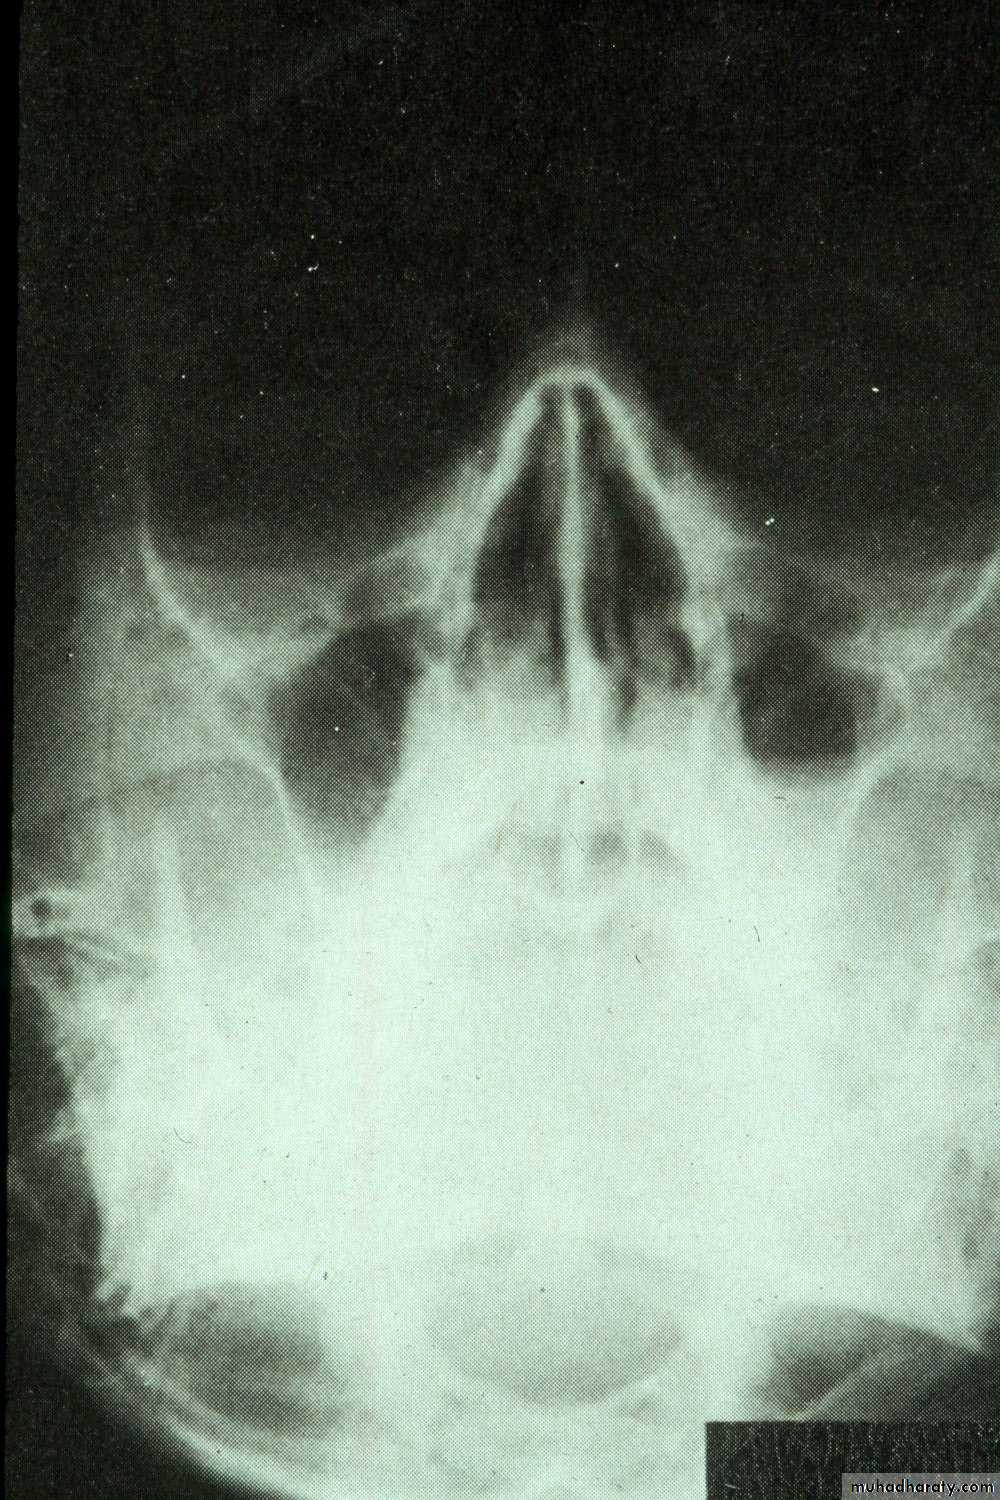

• Occipitomental View (15° OM): it’s called Water’s view. The presence of pus will produce a horizontal fluid level in this view; provided that there is air above it. As a measure of confirmation of the diagnosis, the view is repeated with the head tilted toward the side of pathology. The fluid level remains horizontal.

Water’s view with air-fluid level in left maxillary sinus